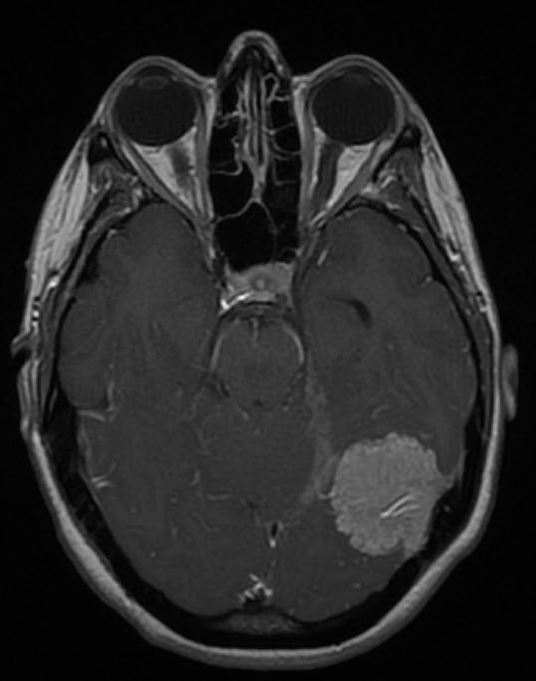

腦膜瘤

小腦腦膜瘤嚴重嗎?出國治療腦膜瘤哪個醫(yī)院好?

小腦腦膜瘤嚴重嗎?出國治療腦膜瘤哪個醫(yī)院好

小腦腦膜瘤嚴重嗎? 出國治療腦膜瘤哪個醫(yī)院好?2018年的哈爾濱市新陽路小學五年二班的班主任(邰慧老師)被診斷為腦膜瘤,在治療時需要剃掉頭發(fā),隨后當老師治療完歸來時,27個男...